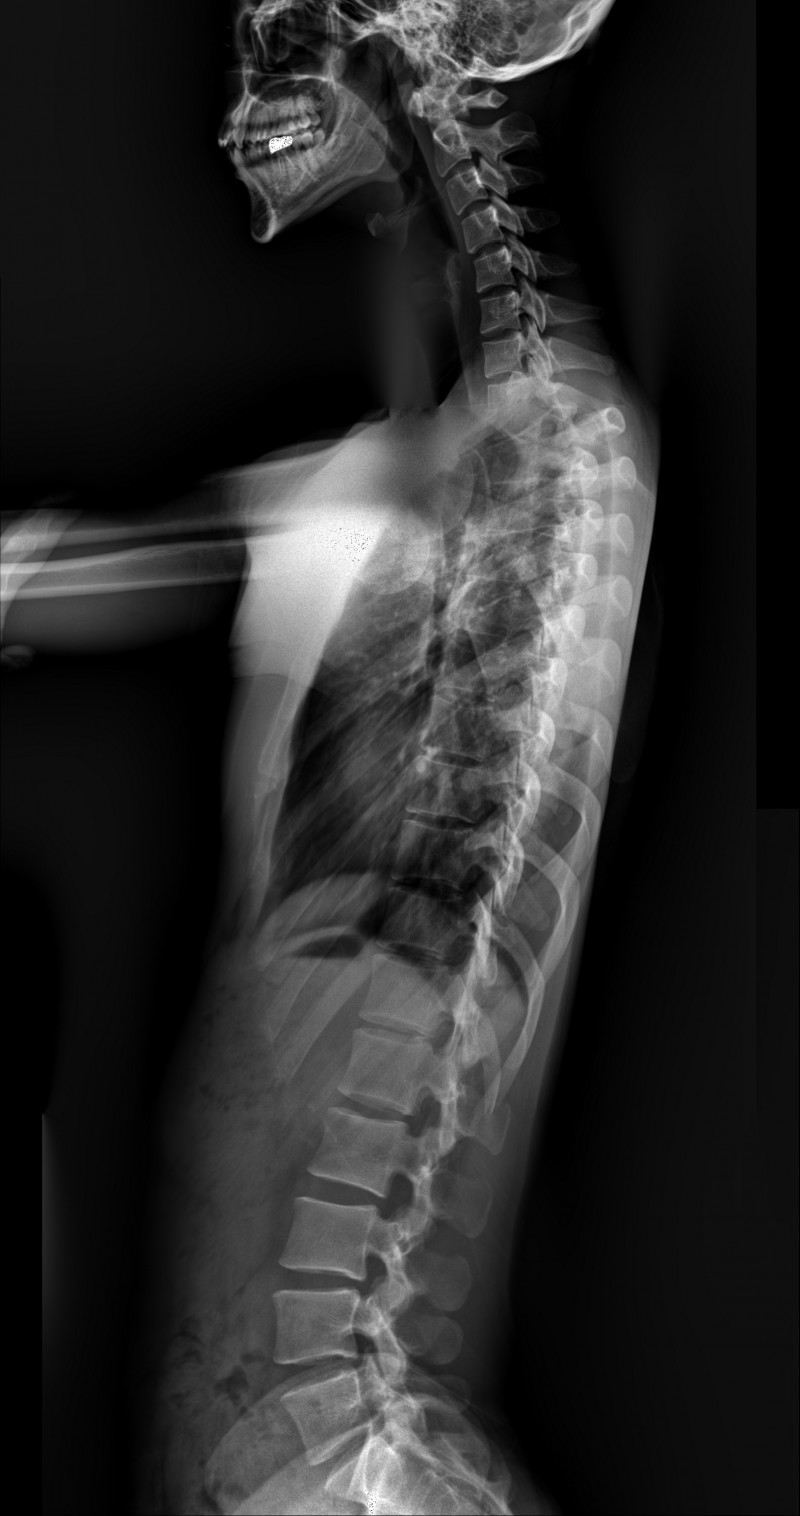

굽은등 역c자커브, 편평등 20대 남성